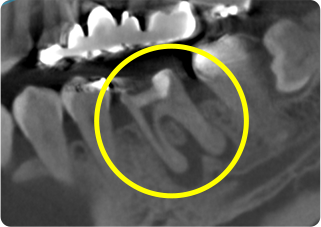

精密根管治療③

術前

術後

| 主訴 | 奥歯で噛むと痛い |

|---|---|

| 治療期間/回数 | 1ヵ月、4回 |

| 価格(税込) | 88,000円(税込) |

| リスク・副作用 | 病変再発、歯根破折の可能性 |

| ポイント | う蝕検知液を用い、むし歯の取り残しが無いようにし、ラバーダム防湿を行い、無菌的に根管治療を行った。根管充填材は、殺菌作用の強い保険適応外のMTAセメントを使用した。 |